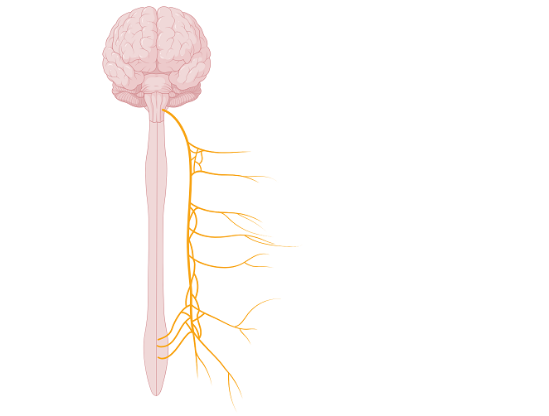

8. Какие симптомы может вызвать повреждение нерва, указанного на рисунке?

нарушение тактильной чувствительности кожи лба

нарушение сокращения трапециевидной мышцы

нарушение отделения желудочного сока

нарушение равновесия

Ответ: нарушение отделения желудочного сока